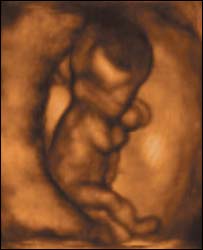

बच्चा 12वें हफ़्ते में अंगड़ाई लेने लगता है

भ्रूण

बारहवें सप्ताह में बच्चा गर्भाशय में 'चलने' लगता है

नए अल्ट्रॉसाउंड स्कैन ने जो तस्वीरें ली हैं उसमें 12 सप्ताह के भ्रूण को गर्भाशय में 'चलते' हुए देखा जा सकता है.

इतना ही नहीं नए स्कैन से यह भी देखा जा सकता है कि माँ के पेट में बच्चा किस तरह जम्हाई लेता है और किस तरह अपनी आँखें मलता है.